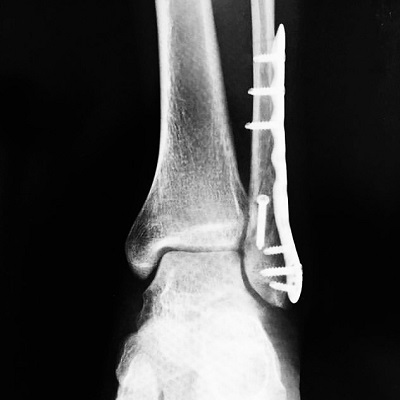

左遠位端骨折抜釘手術

今年1月に左足首を骨折した際に

2×4金物のようなものを足首に埋込み、

離れた骨を繋げる手術をしたのですが、

その2×4金物のようなものを取除く手術をしました。

それまで約10ヶ月間左足首に違和感がありましたが、

取除いたことでとてもスッキリしてます。

何よりも手術をして翌日にはしっかり杖なしで

立つことができたということに感動を覚えました。